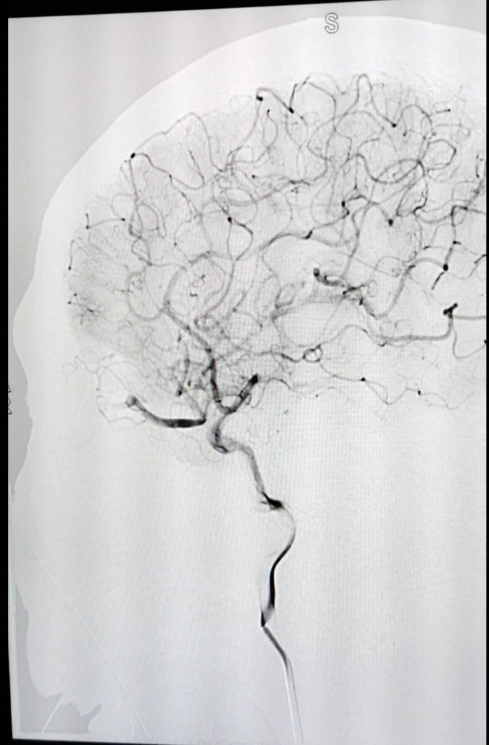

▲从左到右:术后右侧颈内动脉正位造影、术后右侧颈内动脉侧位造影

神经外科二病区在我院先行开展了脑血管造影检查,此次又率先开展神经介入治疗,不仅实现了陇南市及周边地区之前仅仅能做造影检查到现在能够完成介入治疗的重大跨越,而且填补了我市及周边地区介入治疗的空白,也标志着我市乃至甘肃南部地区神经介入发展进入新时代。